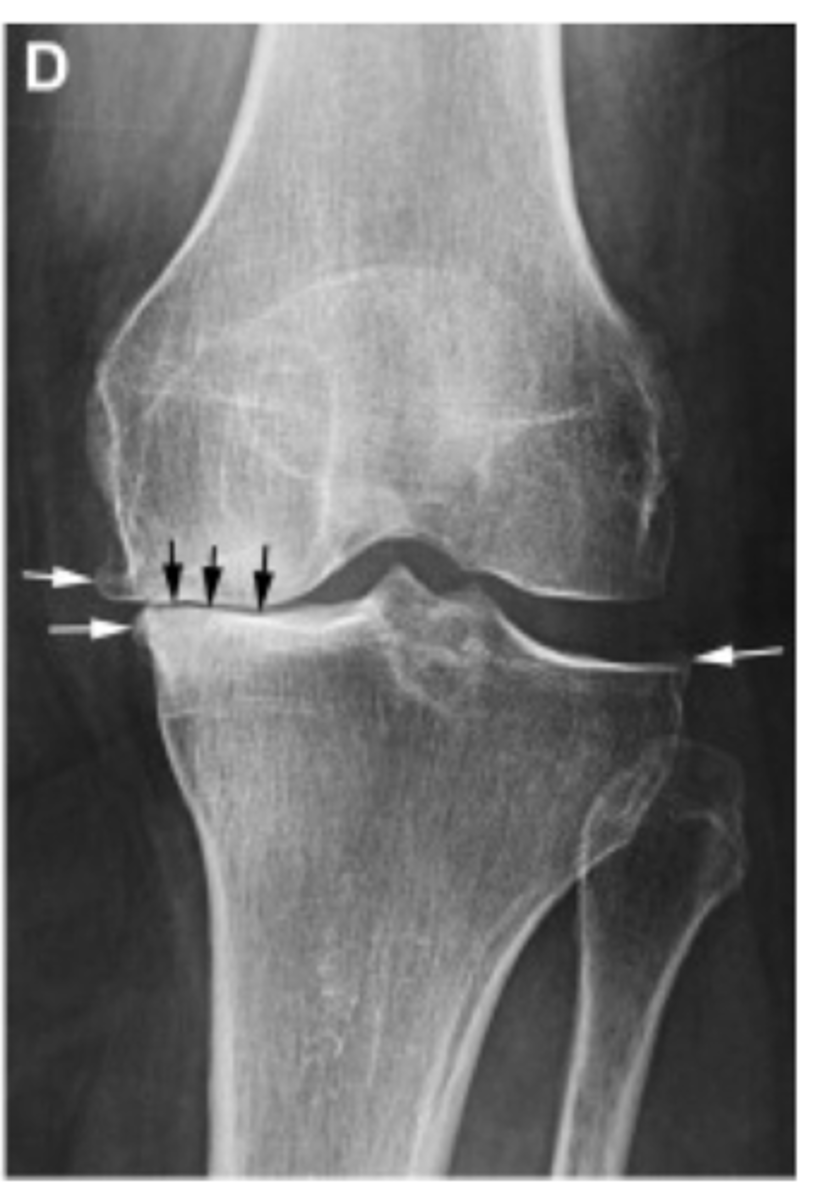

Grade I = minimal osteophytes w/ no problems w/ space or cartilage

Define the Kelgren Lawrence grade. How do you know?

Grade II = 1 definite osteophyte w/ NO space narrowing

Grade III = marginal osteophytes w/ space narrowing + sclerosis & multiple osteophytes

Grade IV = obliteration of joint space (bone on bone)